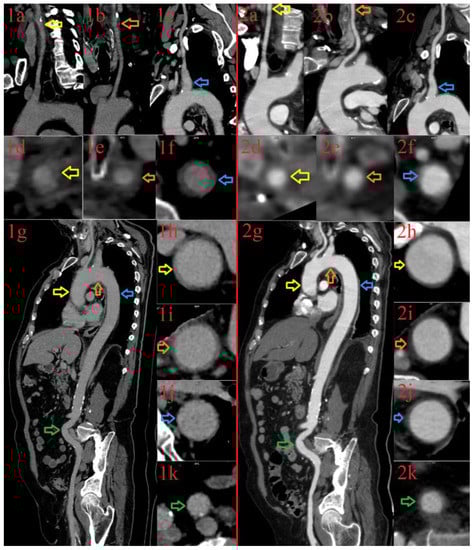

3.1.2. Patient 2

3.1.3. Patient 3